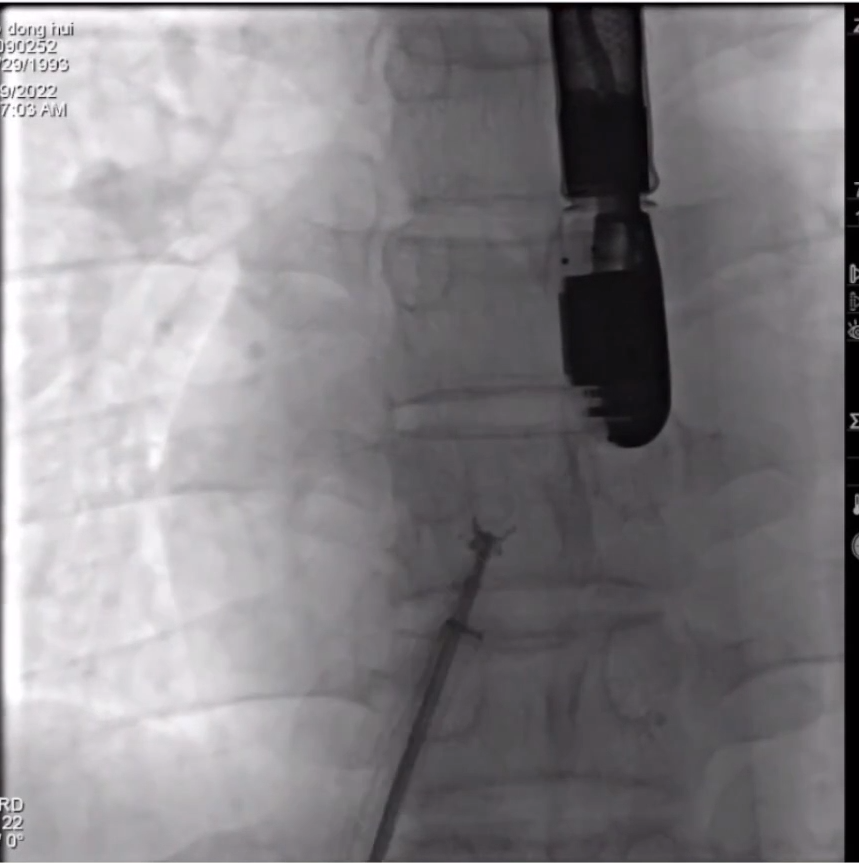

患者男性,29岁,2年前无诱因出现头昏头痛,反复发作,多次就诊未查出病因,近日于合肥高心医院检查确诊患有卵圆孔未闭。

专家团队依据患者病情及各项检查情况,认为患者病情条件符合行卵圆孔未闭封堵术指征,由海军军医大学附属长海医院的秦永文教授主刀,合肥高新心血管病医院周文兵主任团队协作,为患者施行NeoSorb®全降解PFO封堵介入手术。

手术过程

本次手术采用食道超声引导,从患者大腿根部股静脉置入导管,经导管送入NeoSorb®全降解卵圆孔未闭封堵器,超声确认封堵器位置及各项指标良好后,释放封堵器,手术成功,术后超声显示封堵效果理想。

▲封堵器完全释放